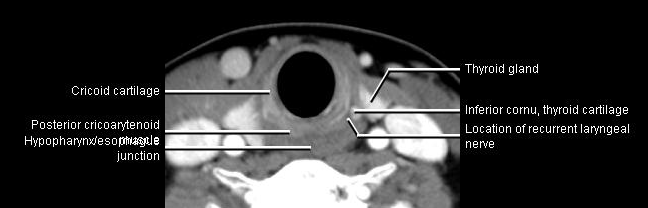

Phonation and dysphagia involve multiple coordinated structures in the larynx and pharynx. Radiation induced dysphagis appears to be related to dose to the phyaryngeal constrictor muscles and specific regions of the supraglottic and glottin larynyx.

Speech is impacted by doses to the epiglottis, base of tongue, aryepiglottic folds, false vocal cords upper esophageal sphincter and cricoid cartilage.

AnatomyCTMR